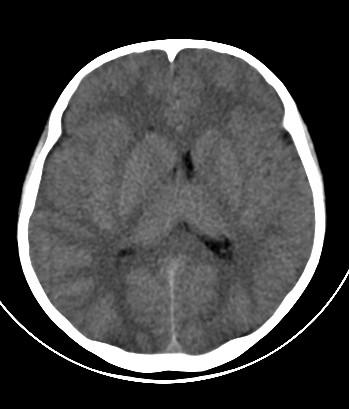

外伤一天,m,21y,骨窗示右颞骨骨折.

请大家看看,是脑内还是脑外(硬膜下还是硬膜外).请说说理由.谢谢.

右侧颞叶大片状形态不规则高密度影,边缘较模糊,无明显白质挤压移位。支持脑错裂伤、脑内血肿。

右侧颞叶大片状形态不规则高密度影,内缘较模糊,外缘紧贴颅板,无明显白质挤压移位伤。

依据:1.右侧颞叶不规则形血肿密度影,周围有水肿;

2.有明显占位效应;

3.颅板下硬膜下间隙存在。

右颞叶见混杂密度灶(以高密度灶为主)右侧脑室受压变形,中线结构左移,右颞部颅骨内板下见弧形高密度灶,右侧裂池及部分脑沟内见高密度灶;

结论:1:右颞叶脑挫裂伤;

2:右侧硬膜下血肿;

3:蛛网膜下腔出血。